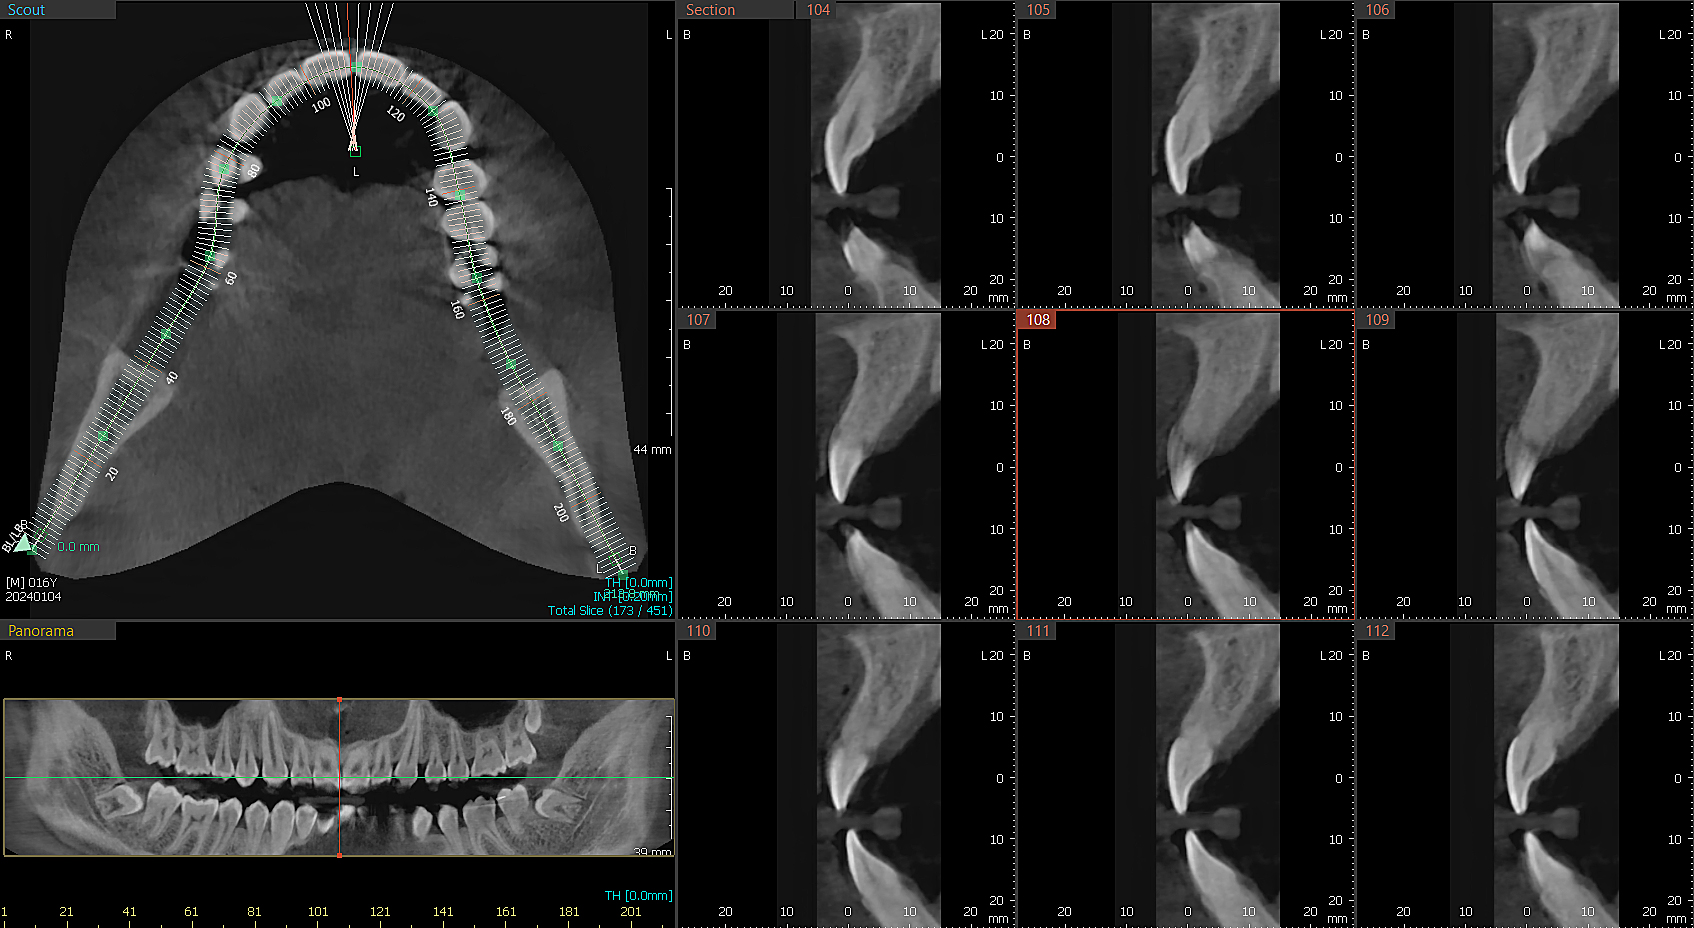

CBCT-3D

Tomografie Computerizată cu Fascicul Conic este o tehnică avansată de imagistică dentară care furnizează imagini tridimensionale (3D) detaliate ale structurilor dentare și osoase.